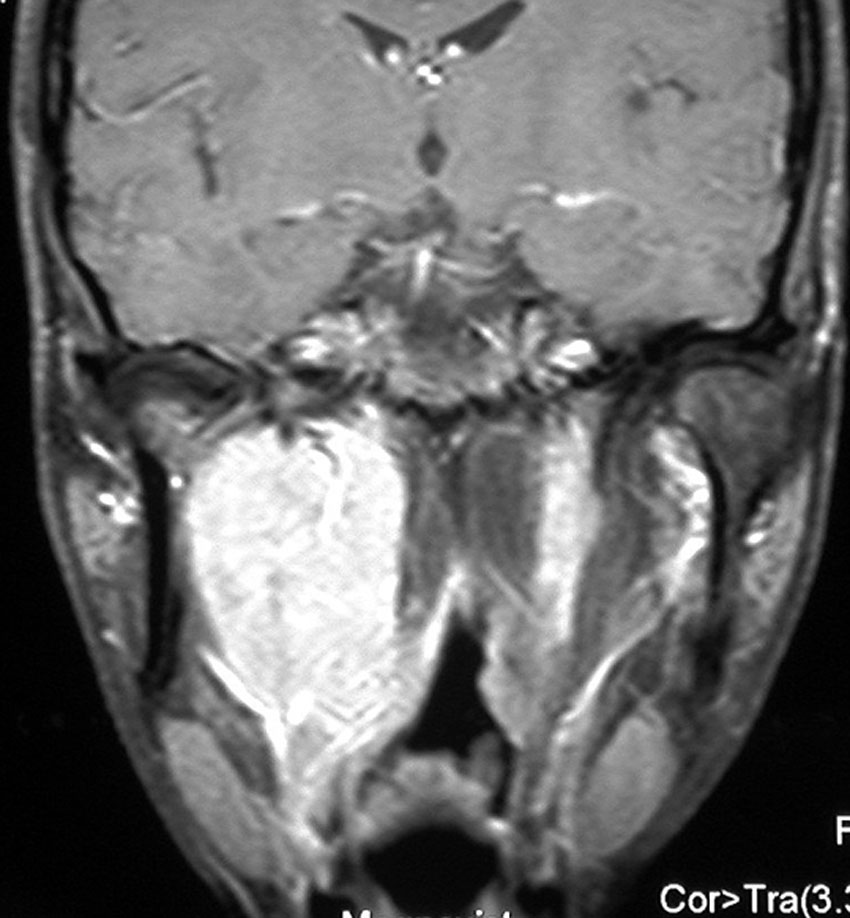

遺伝歴があり30代くらいです。黄色の矢印で示す右側はglomus vagale,左側は上がglomus jugulare、左下がglomus caroticumです。教科書に載せたいくらい典型的な部位に発生しています。無症状ですからもちろん治療はしません。6年くらい経過観察していますがほとんど増大もしません。